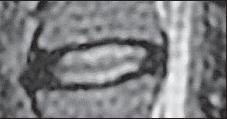

МРТ № 4

На МРТ № 4 наблюдается межпозвонковый диск в начальной стадии развития дегенеративно-дистрофического процесса.